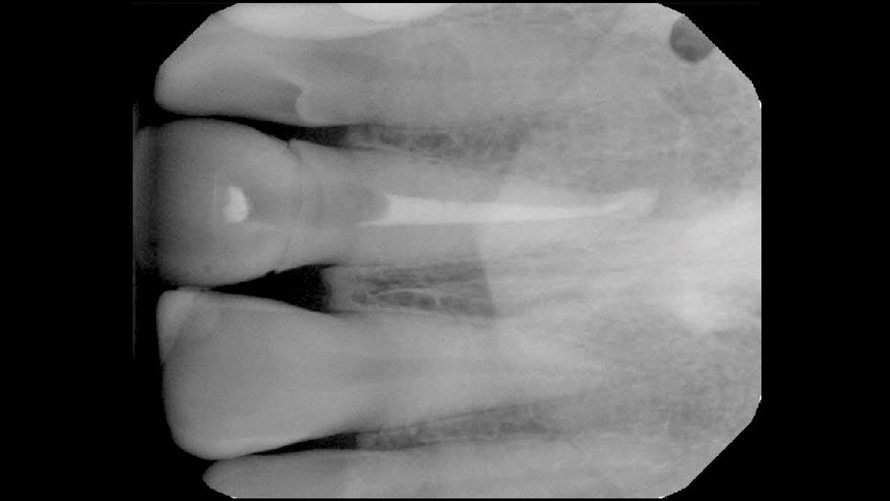

(3.) Case 1: Preoperative radiograph of the maxillary right central incisor, demonstrating periapical radiolucency and porous core buildup.

Figure 3

In the first case, the patient reported a history that included childhood dental trauma without swelling or discomfort. The intraoral examination indicated that the existing all-ceramic restoration on tooth No. 8 possessed an inappropriate morphology, surface topography, and shade. Radiographically, tooth No. 8 exhibited a large underlying resin core with significant porosity and periapical radiolucency (Figure 3). The diagnosis for tooth No. 8 was pulp necrosis with asymptomatic apical periodontitis.